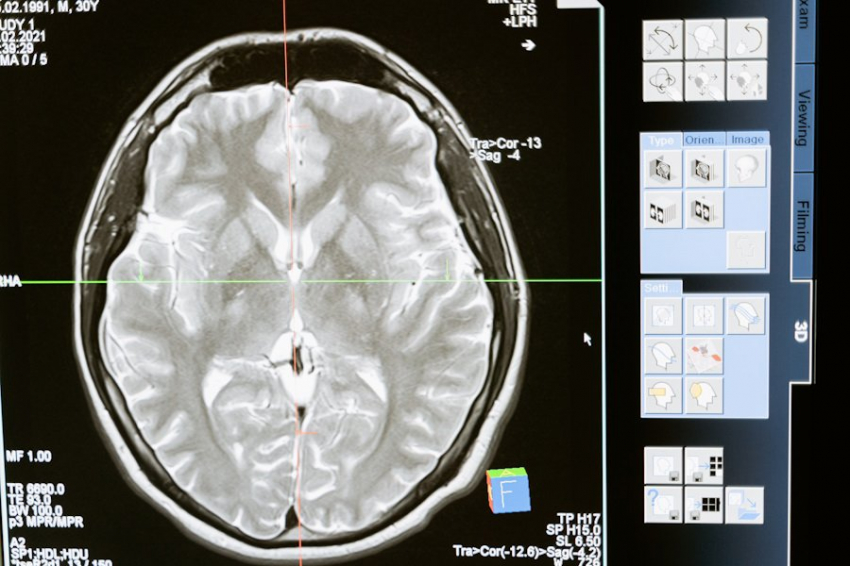

Исследователи из Мичиганского университета раскрыли новые детали влияния анестетика пропофола на работу мозга. Группа ученых провела эксперимент с использованием функциональной магнитно-резонансной томографии (фМРТ), чтобы изучить изменения в мозговой активности здоровых добровольцев на разных этапах седации пропофолом.

Результаты исследования показали, что во время глубокой седации происходит значительное снижение активности определенных нейронов в таламусе. Эти нейроны отвечают за интеграцию сенсорной информации, поступающей из различных источников. Интересно, что при этом обработка отдельных сенсорных сигналов продолжается, но нарушается процесс их объединения в целостную картину.

Особое внимание ученые уделили так называемым матричным клеткам таламуса. Выяснилось, что именно эти клетки играют ключевую роль в переходе человека в бессознательное состояние под действием пропофола. Матричные клетки имеют обширные связи с высшими отделами коры головного мозга и, как оказалось, критически важны для поддержания сознания.